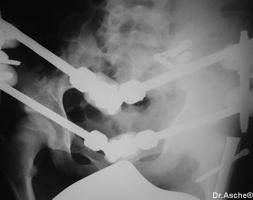

Vordere und hintere Beckenringfraktur bei Polytrauma. Hier ist die Stabilisierung mit Fixateur allein nicht stabil genug. In einem solchen Fall sollte zuerst die hintere Fraktur mit Platte, Schrauben oder wie in diesem Fall mit mit einer Drahtgurtung stabilisiert werden. Danach wird der Patient in Rückenlage gebracht und der Beckenring vorne mit einem Fixateur befestigt. Belastung ist meist nach 4-5 Wochen möglich.